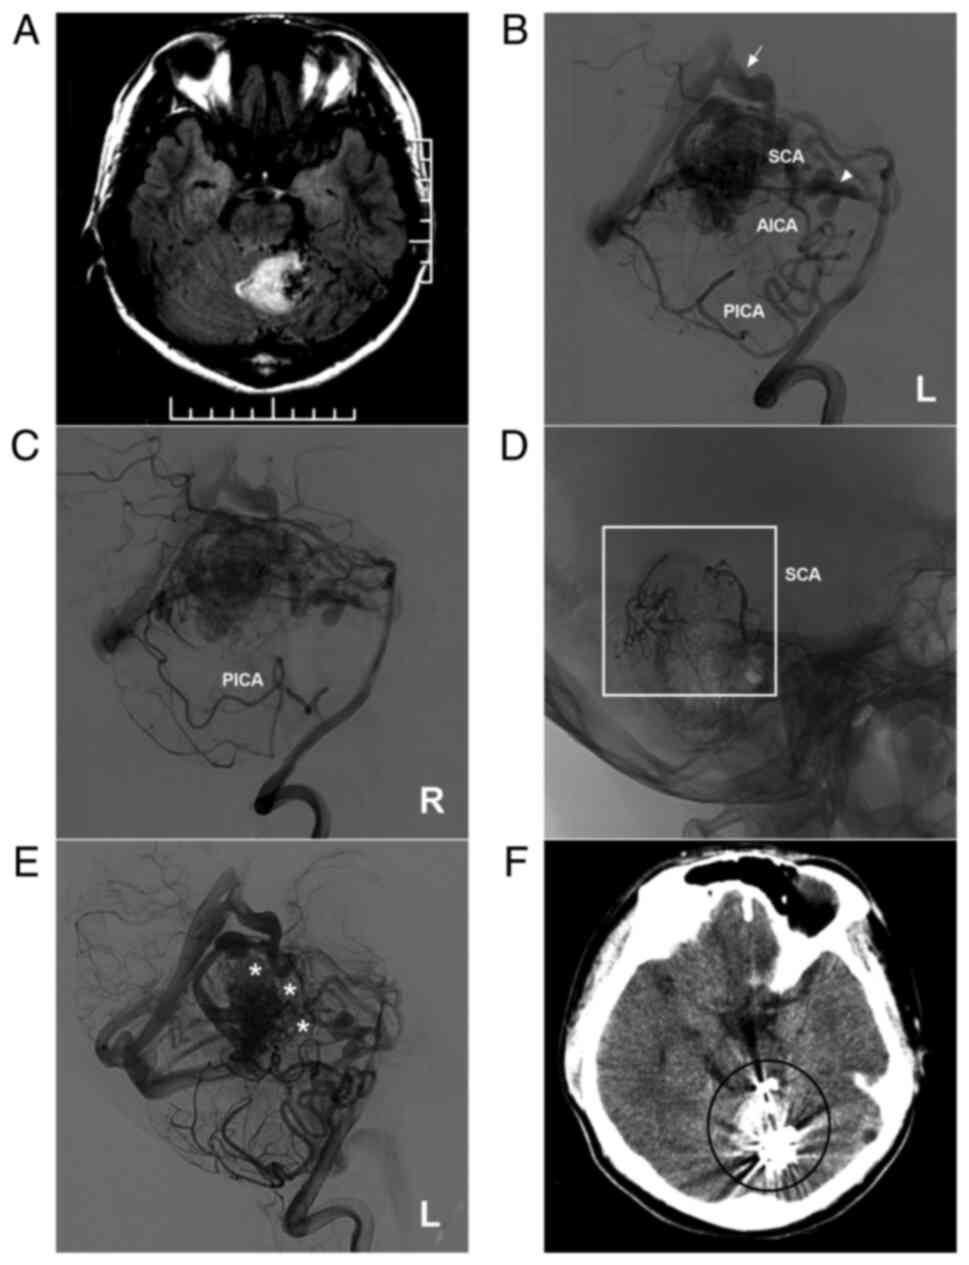

Figure 3

AVM in the middle cerebellum with a mixed blood supply from the SCA and AICA. (A) CT scan showing a subarachnoid hemorrhage and right cerebellar vermis hematoma. (B) DSA of the left vertebral artery shows the AVM supplied by the SCA and AICA. (C) DSA of the late arterial stage shows the draining veins (arrows). (D) Three-dimensional reconstruction DSA showing Onyx™ casting (ellipse) through the SCA. (E) DSA after embolization showing a small amount of residual AVM nidus. (F) Post-operative CT scan showing that the hemorrhage was absorbed, but had a dilated ventricle. The case presented in this figure was a 20-year-old female who had a sudden headache. EVT was performed. No EVT complication was observed. Currently, the woman exhibits normal healthy features and attends university. Radiotherapy was suggested. AICA, anterior superior cerebellar artery; AVM, arteriovenous malformation; CT, computed tomography; DSA, digital subtraction angiography; L, left; SCA, superior cerebellar artery.